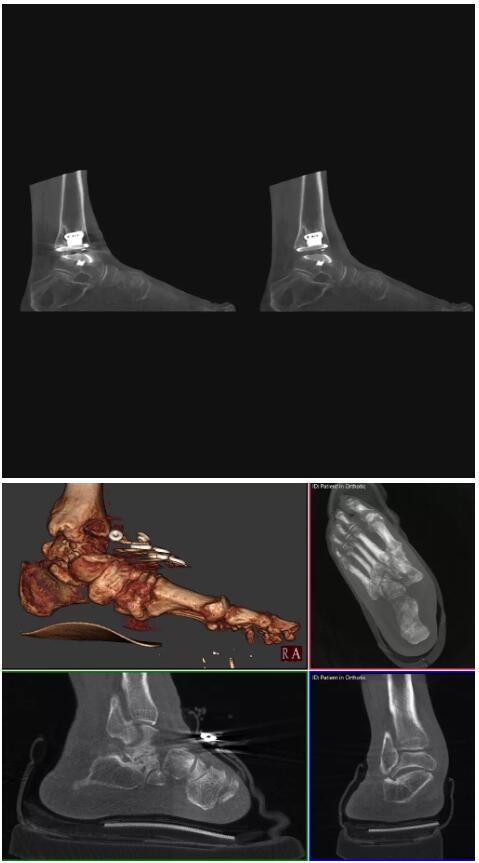

比如上面這款專用于足部和踝部掃查的CT成像系統(tǒng),患者在進行CT掃查時只需要站在上面即可,雙腳站或者單腳站都可以,當然,如果患者不是那么方便站著做完CT掃查,也可坐在上面。

這款CT掃查系統(tǒng)自帶屏蔽裝置,它的體積非常小,僅需要極小的空間即可,并不像常規(guī)CT那樣需要一間單獨的檢查室。此外,這種CT掃查的速度非???,僅需30秒左右可以完成檢查,輻射劑量相對常規(guī)的CT要少許多,尤其適合醫(yī)院的骨科使用。

而患者站著做足部或者踝部做CT檢查還有個好處是,可以檢查患者在負重的情況下,骨關(guān)節(jié)的真實情況,而躺著做CT掃查時未必能看出來。負重CT掃查特別是對于受傷的運動員或者舞蹈員來說意義更大,能夠更準確地評估傷情,幫助他們盡早復(fù)原。

以下是這些“特立獨行”的CT所拍出來的圖像: